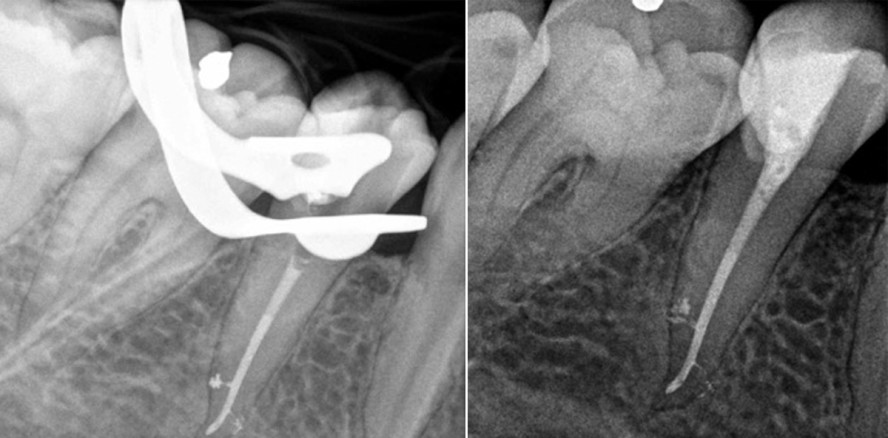

Der jugendliche Patient konsultierte uns mit starken Beschwerden am Zahn 47. Der Zahn war endodontisch vorbehandelt. Auf dem Ausgangsröntgenbild musste eine chronische apikale Parodontitis festgestellt werden (Abb. 9). Nach Entfernung der alten Wurzelfüllung wurden die Kanäle maschinell bis 20.04 (PathFile, DENTSPLY Maillefer) aufbereitet (Abb. 10), nach bekanntem Protokoll gespült und eine medikamentöse Einlage mit Kalziumhydroxid (Calxyl) eingebracht. Nach dem provisorischen Verschluss konnte der Patient vorerst aus der Praxis entlassen werden. Vier Wochen später war er beschwerdefrei und die Behandlung wurde fortgesetzt. Nach der Anästhesie sollte die finale Aufbereitung der Wurzelkanäle mit der SAF erfolgen. Allerdings wurden zunächst unbehandelte Kanäle gefunden. Die mesiale Wurzel des Zahnes hatte vier Kanäle. Die Aufbereitung aller Wurzelkanäle mit der SAF erfolgte identisch zu bereits beschriebenem Vorgehen. Da die Reinigung und Spülung bei der SAF mit einer geringen Krafteinwirkung auf die Kanalwände erfolgt, ist nahezu kein apikaler Transport von Debris zu erwarten.2 Damit eignet sich die Feile auch dafür, medikamentöse Einlagen aus dem Kanallumen zu entfernen, so wie in diesem Fall. Danach wurden die mesialen Kanäle bis ISO 35 und die distalen Kanäle bis ISO 40 aufbereitet und der Zahn erneut mit einer medikamentösen Einlage verschlossen. Zwei Monate später konnte die Behandlung abgeschlossen werden. Das Röntgenbild zeigte deutliche Heilungstendenzen (Abb. 11). Die Füllung der Wurzelkanäle erfolgte mit Guttapercha und AH Plus in warmer vertikaler Obturation mittels modifizierter Schilder-Technik. Der Patient konsultierte die Praxis nach sechs Monaten zur Kontrolle. Das Röntgenbild bestätigt den Erfolg der Behandlung (Abb. 12). Der Zahn konnte trotz ungünstiger Ausgangslage erhalten werden.